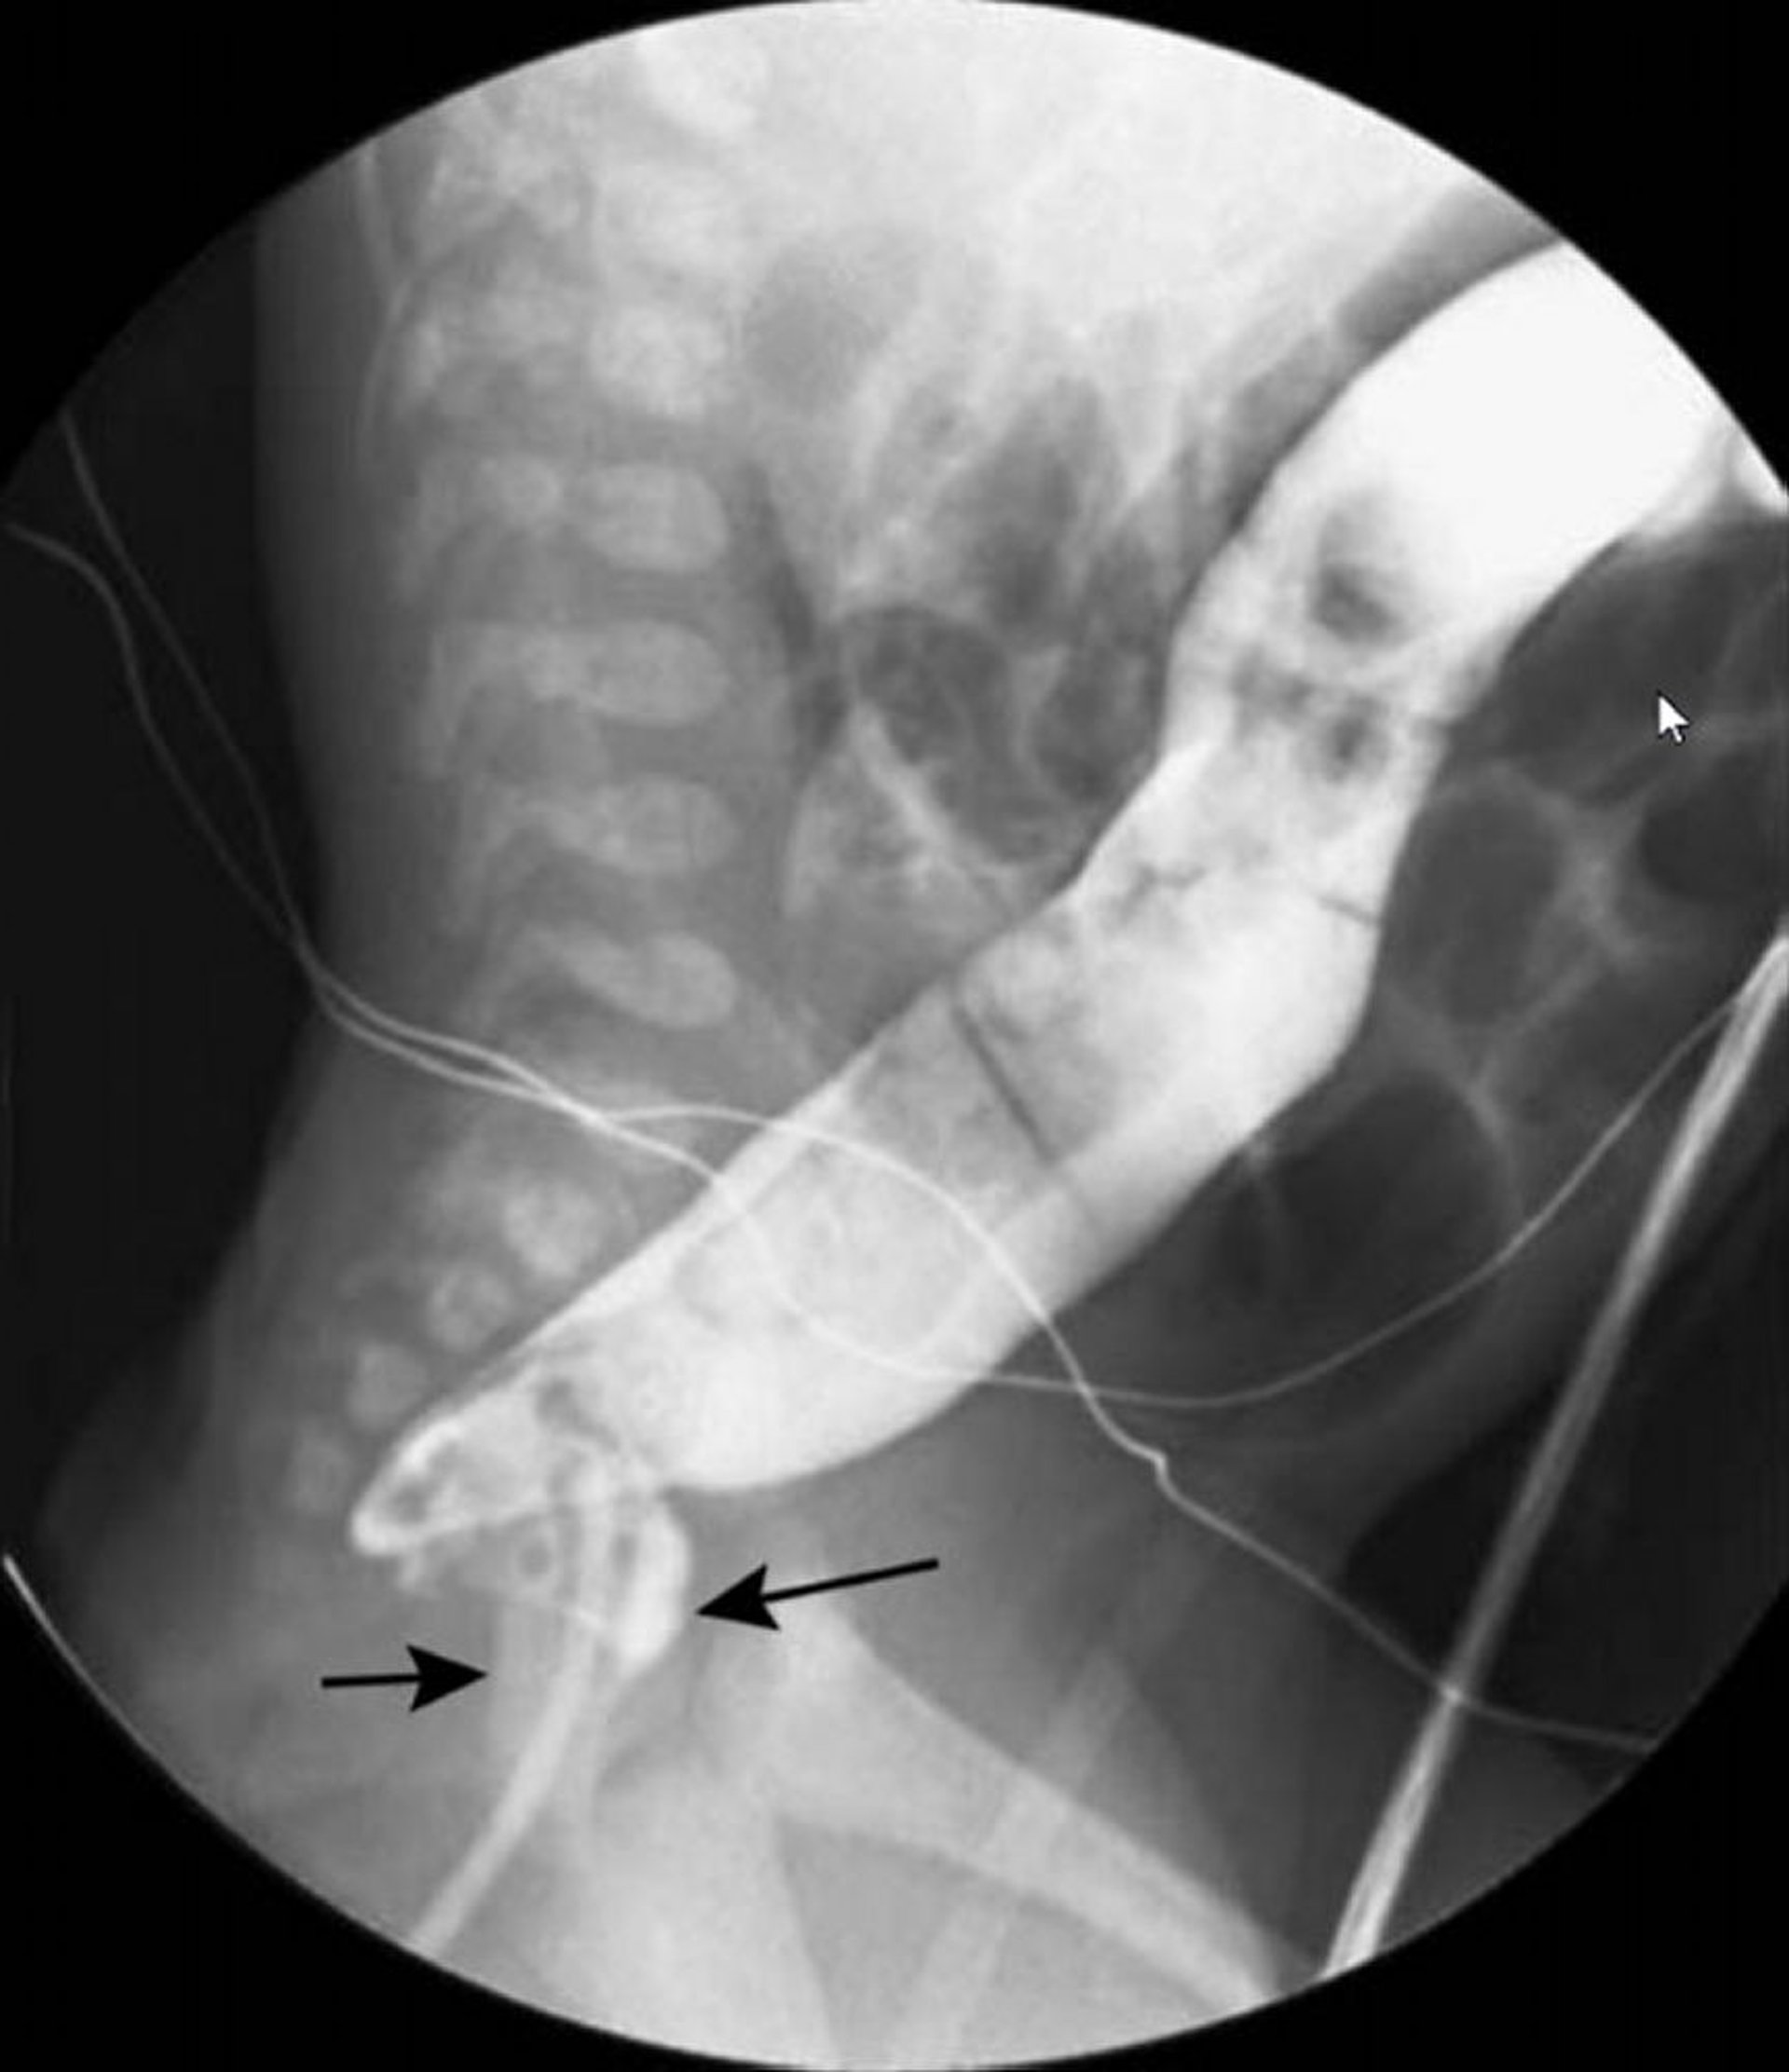

Enema de bario con un solo medio de contraste que muestra el aspecto en cuello de cisne de la enfermedad de Hirschsprung

En esta imagen, el enema de bario muestra un recto estrechado (flechas negras) y un colon dilatado (flecha blanca) más proximal.